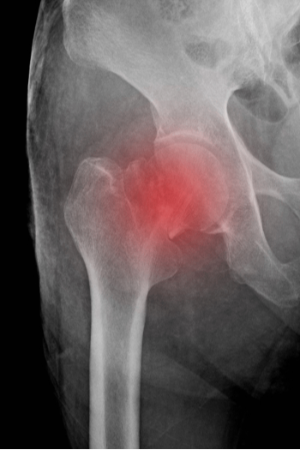

Arthroplasty

A comparison of THA vs HA treatment of displaced femoral neck fractures in patients over 75 years

Short Stem vs Conventional Femoral Stem in THA for Patients with Osteonecrosis of the Femoral Head

Orthop Surg. 2020 01-Jun;():. 10.1111/os.12684

Corticosteroid Injection for Hip OA is Effective for Improving Pain, Function, and Quality of Life

Arthritis Rheum. 2007 28-Jun;():. 10.1002/art.22739